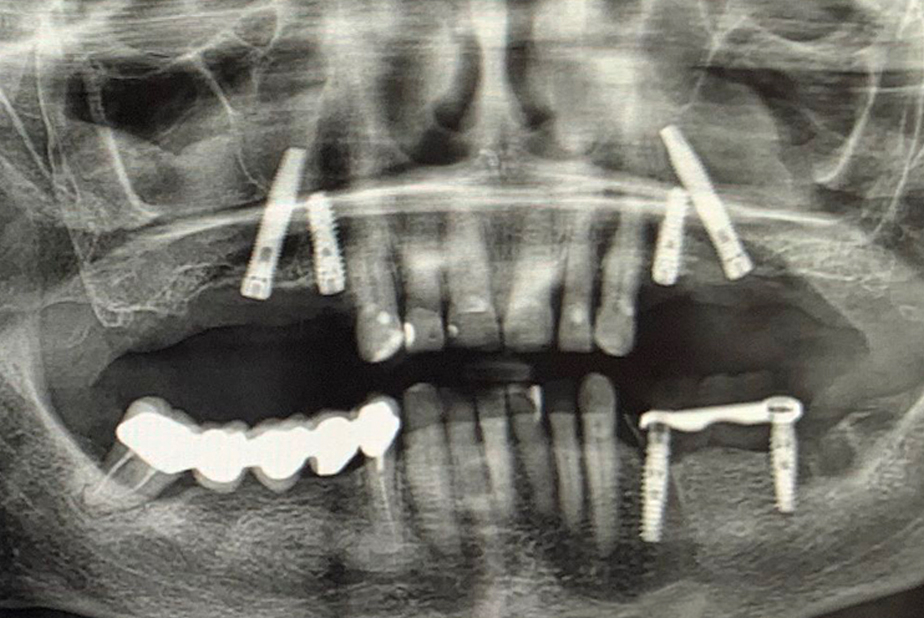

A seguito di un'accurata valutazione clinica e radiografica preparatoria (Fig. 1) è stato pianificato l'inserimento di impianti IS+ (BTK) nelle regioni anteriori e di impianti BT-Rhyno (BTK) nei settori posteriori mediante tecnica transinusale.

Valutazione clinica e radiografica preoperatoria

Fig. 1 - Valutazione clinica e radiografica preoperatoria